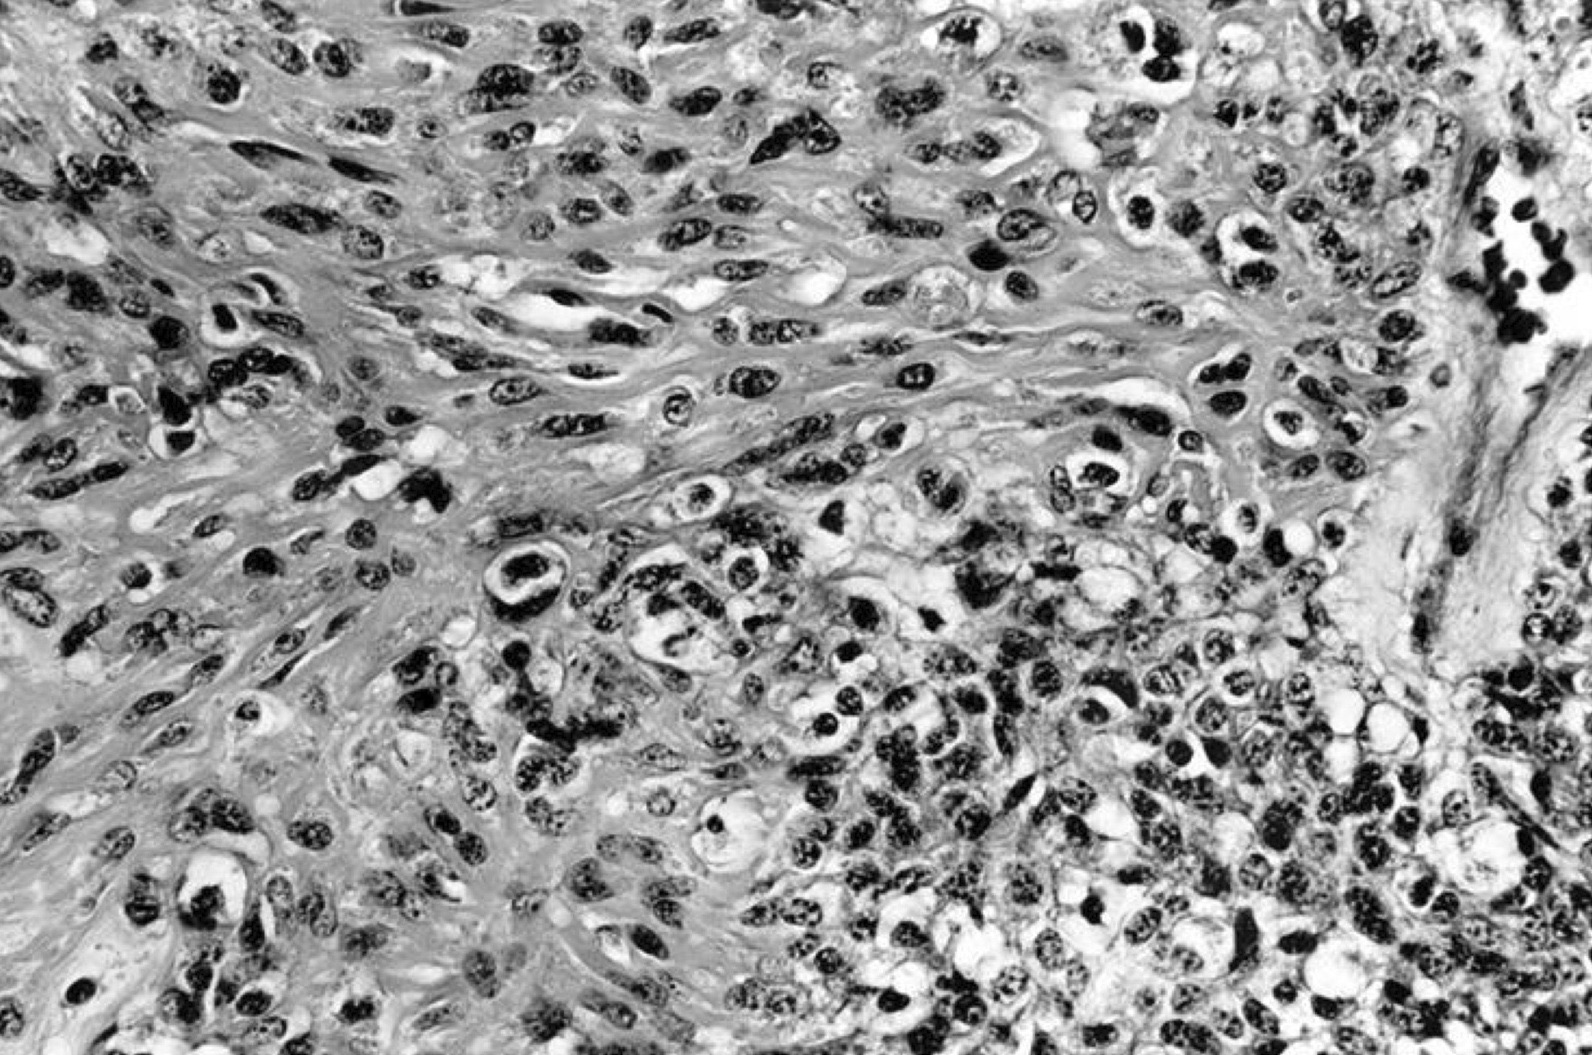

Microscopic (histologic) images

Contributed by Shipra Agarwal, M.D., Andrey Bychkov, M.D., Ph.D., Mark R. Wick, M.D., Asmaa Gaber Abdou, M.D. and AFIP

Patterns:

Atypical adenomas:

Not invasion: